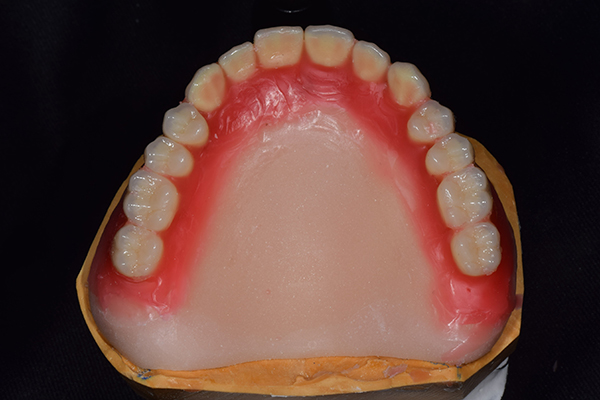

ですのでいざ出来上がってみると見た目が変だったり、噛み合わせがおかしいといったことがでてきやすいのです。 また、左の写真は総入れ歯で自費の入れ歯ですが、このように金属を使うことで入れ歯の厚みを薄くすることができます。

薄くすると、違和感が少ないのと、金属を使うことで、食べ物のの温度を上顎に伝えられるというメリットがあります。 その他、マグネット(磁石)やインプラントを使った入れ歯ですと、パカパカ外れにくいといったことを解消できます。

完成した入れ歯とかぶせ物です。 入れ歯への寛容度が高い患者様でしたので、 金属は使用せず、プラスチックのみで上は仕上げました。 下顎も歯は1本減ってしまいましたが、しっかり 入れ歯が維持できる様な構造にしました。

入れ歯は極力薄くするために金属を使用しました。しっかり噛める様にするため、ノンメタルクラスプデンチャーにはしませんでした。

上の入れ歯(表)

上の入れ歯(裏)